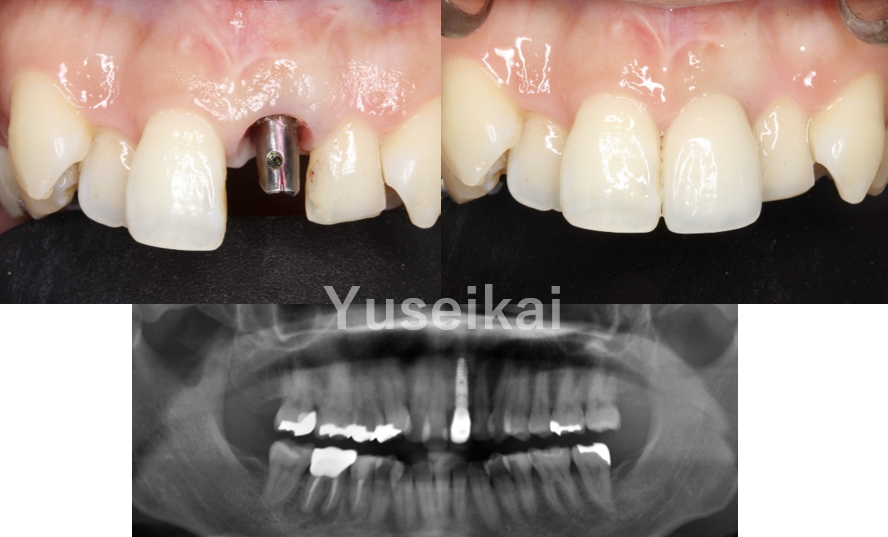

抜歯即時埋入

抜歯即時埋入とは、抜歯と同時にインプラントを埋入する方法です。従来のインプラント治療では、抜歯後に骨の回復を待つ必要があるため治療期間が長くなりますが、抜歯即時埋入では治療にかかる期間を大幅に削減することができます。これにより、患者様の身体的負担が軽減され、早期から通常の機能回復が期待できます。